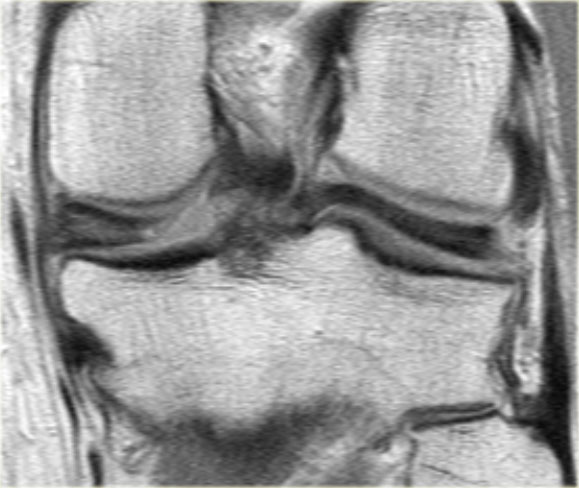

Hãy quan sát hình ảnh bên trái và cố gắng xác định vấn đề của sụn chêm này là gì.

Sau đó tiếp tục xem các hình ảnh liên tiếp tiếp theo của cùng bệnh nhân này.

Như bạn đã đoán được qua tiêu đề của đoạn này, đây là một trường hợp sụn chêm lật (flipped meniscus).

Sụn chêm lật là một dạng đặc biệt của rách dạng quai xô (bucket-handle tear).

Sụn chêm lật xảy ra khi mảnh vỡ của sừng sau bị lật ra phía trước, khiến sừng trước của sụn chêm có vẻ to hơn bình thường.

- Thân sụn chêm ngoài.

- Sừng sau quá nhỏ và sừng trước có vẻ to hơn với đường viền không đều.

- Thoạt nhìn có vẻ như có một đường rách dọc ở sừng trước, nhưng thực chất phần sau của cấu trúc này chính là phần lật của sừng sau bị rách.

Cấu trúc phía trước là sừng trước.

Cũng cần lưu ý tình trạng phù tủy xương khu trú và dấu ấn lõm sụn khớp. - Cấu trúc phía trước là sừng trước.

- Một số bất thường ở phần sau.

- Phần sau di chuyển về phía đuôi (caudal).

- Trong hố gian lồi cầu là điểm nối giữa mảnh di lệch và phần còn lại của sừng sau.